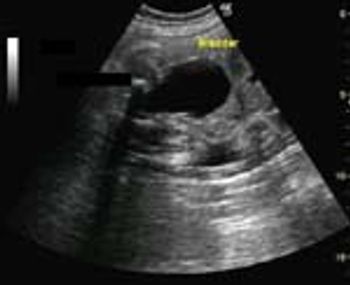

What is your diagnosis of this fetal kidney?